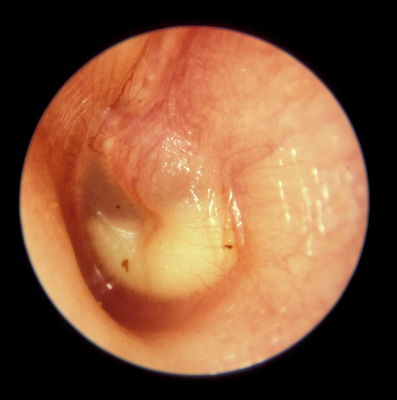

Question 50

Question

tipo de otitis que se observa en la imagen

Answer

• otitis media serosa

• otitis media mixta

• otitis media purulenta